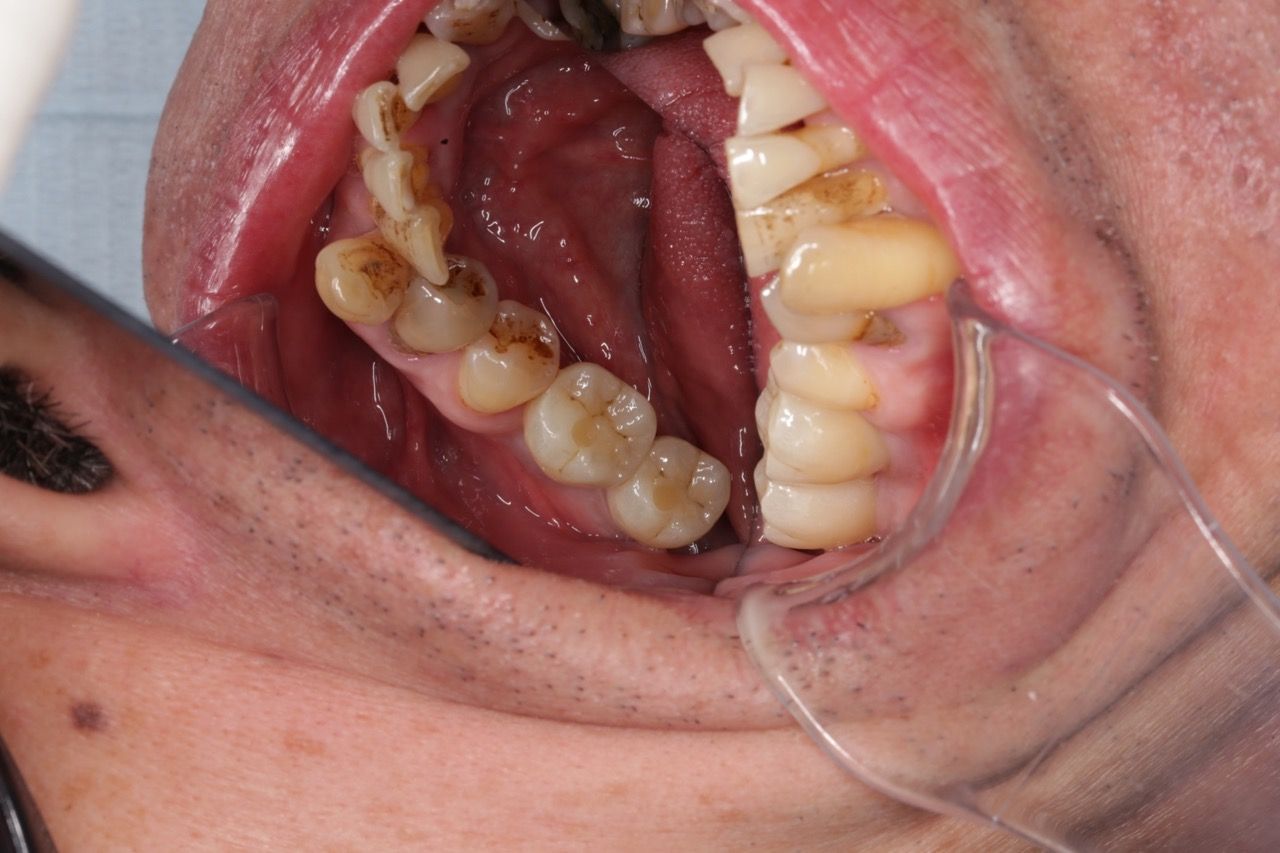

左上拔牙補骨後再植牙 右下即拔即種